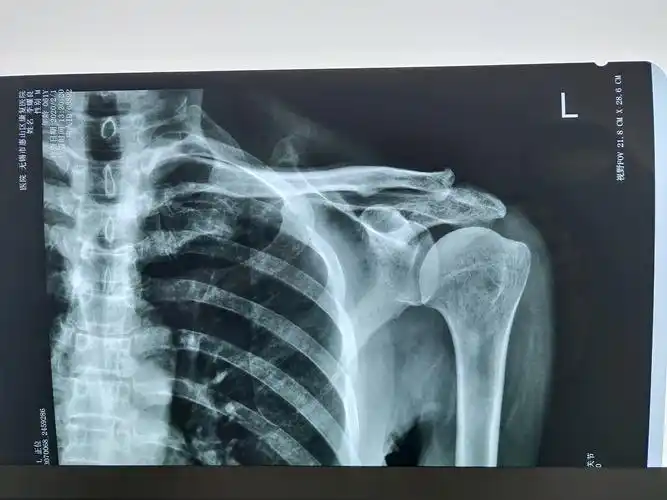

突发肩锁关节剧痛会是痛风性关节炎吗?